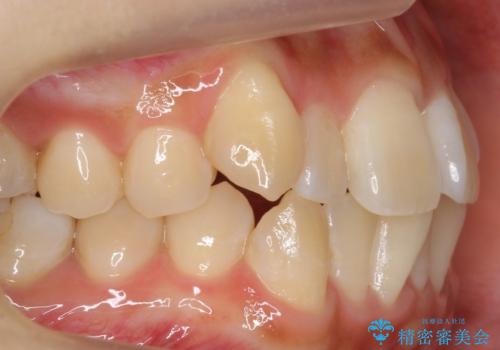

八重歯をインビザラインで 抜歯矯正

- 八重歯を主訴に来院。

出来るだけワイヤー矯正を避け、抜歯も最小限の本数をご希望でした。

下の前歯のみ1本抜歯しています。

下の前歯の周りの骨は薄いことが多く、無理に並べると唇側の骨がやせて歯ぐきが下がり歯が長く見えます。

それを回避するために今回は下顎前歯を一本抜歯をしています。